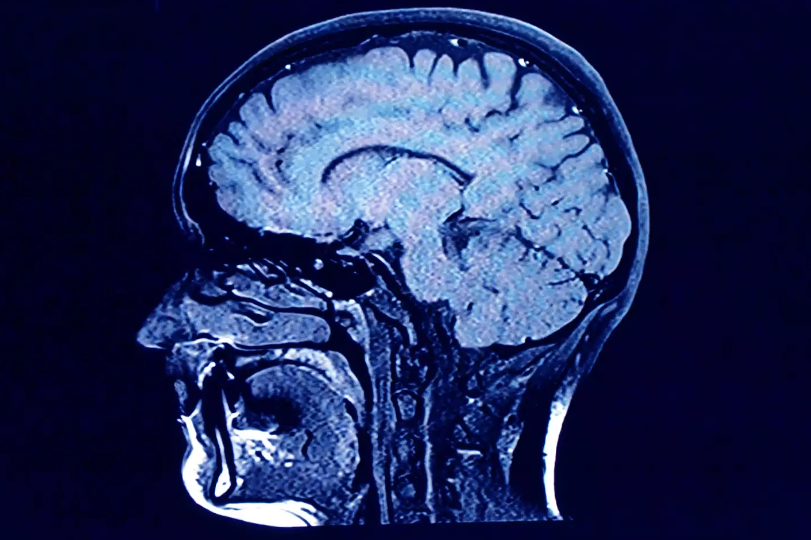

- Brain: The vascular effects of smoking extend to the brain, increasing the risk of strokes, blood clots, and aneurysms. These conditions can lead to severe neurological deficits and are life-threatening.